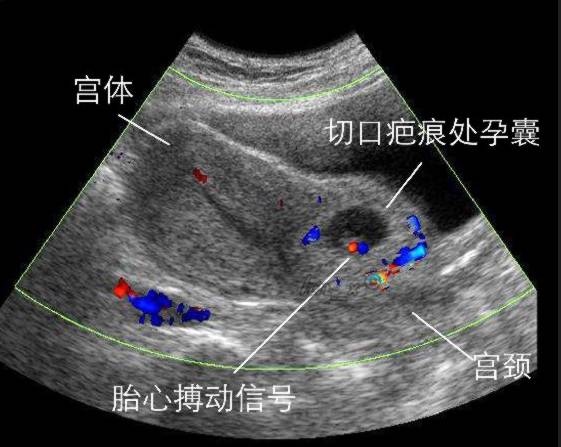

“特殊孕妇”求医为何屡被拒?

近日,烟台海港医院妇产科收治了一位“特殊”的患者,她43岁,10年前做过剖腹产手术和子宫肌瘤剔除术,这次患者已经停经42天了,出现了呕吐和轻微腹痛的感觉,她立马去了龙口当地的小诊所做了B超检查,却发现孕囊长在切口上,并告知刘女士赶紧到大医院进一步的确诊,如果治疗不当是要出人命的。意识到了问题的严重性,刘女士第二天便到了烟台某家医院进行检查、治疗,但由于医院的技术条件有限,建议患者转院到烟台海港医院再次就诊。

接待刘女士是郭建红医生,先了解了病史、详细病情后便安排她做了相关检查。但郭医生内心深知瘢痕妊娠的风险比宫外孕有过之而无不及,一直是让所有妇科大夫最头痛的问题,稍有不慎就会有大出血的风险,甚至有可能切掉子宫。随即安排了与刘女士及其家属进行严肃的谈话,告知目前刘女士确诊为瘢痕妊娠。瘢痕妊娠,通俗地讲就是受精卵着床的位置错了在剖宫产的疤痕处。刘女士和丈夫慌张地问:“就是孩子保不住了是吗?”郭建红医生严肃地说,这个孩子不仅不能保,反而胚胎越大对母体危害越大。因为瘢痕妊娠早期或无症状,与正常妊娠相似,随着胚胎的发育会导致孕妇可能出现阴道不规则出血或急剧腹痛等,当然也因人而异,如果没有及时诊断治疗不当的患者有可能术中大出血,甚至要切掉子宫的。为了争取最好的结果,当务之急,我先向袁主任汇报你的病情再决定治疗方案,袁主任听完病情汇报,立即召集妇科几位专家对刘女士的病情进行讨论和分析,最终专家组一直认为为了减少患者的创伤和痛苦,采用奥洛克超导多弹头系统微创治疗,并做好了一切预案。